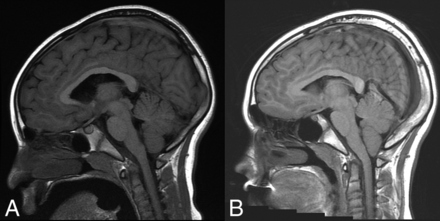

The literature describes multiple reports of “acquired” Chiari I malformations in the setting of spinal CSF drainage (eg, ventriculoperitoneal shunts). Images from these reports do show cerebellar descent, but many also show findings of intracranial hypotension. Overshunting, in which CSF diverted at a rate greater than production, results in an iatrogenic cause of intracranial hypotension or hypovolemia. The underlying physiology is similar to that of SIH (though iatrogenic in origin) and shares similar findings of slit-like ventricles, effacement of the subarachnoid spaces in the posterior fossa, flattening of the ventral pons, and descent of the brain stem and tonsils (Fig 2).

“Acquired” Chiari malformation showing findings of CSF hypotension. A, Sagittal T1WI demonstrates a normal appearance of the posterior fossa of a 6-year-old patient with a ventriculoperitoneal shunt. B, Six years later, imaging demonstrates findings of overshunting resulting in CSF hypotension. This has previously (mistakenly) been called “acquired Chiari malformation.” In addition to descent of the tonsils, there is also effacement of the subarachnoid spaces, flattening of the pons, descent of the brain stem, and a decrease in the volume of the lateral and fourth ventricles, all of which indicate reduced CSF volume.